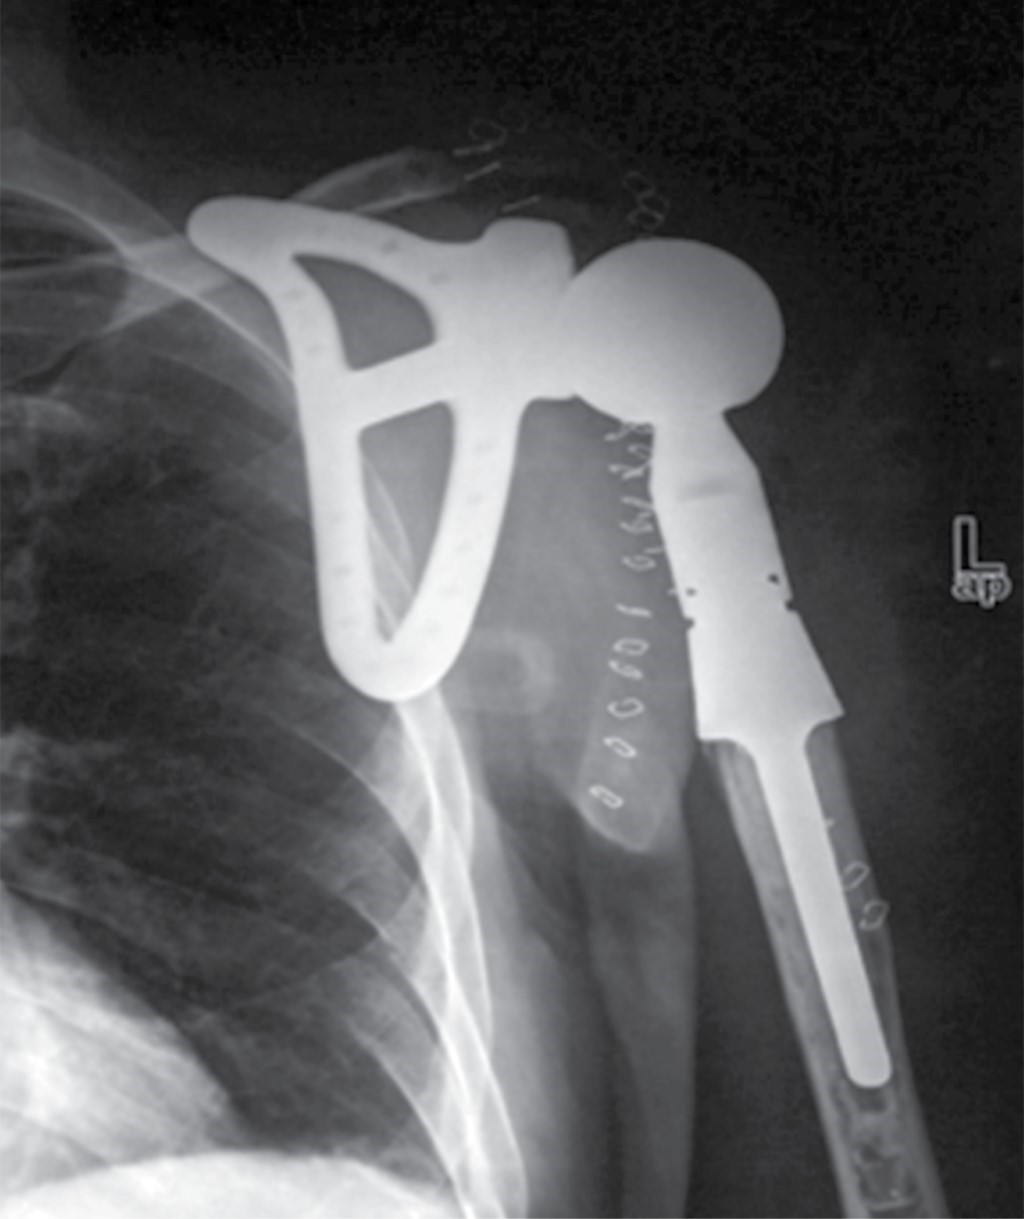

The approximate incidence of this case is 2-5:1'000,000, so it is a very rare entity. In studies where the use of the Tikhoff-Linberg type 4 technique is reported,10,11 scapula and/or humerus prosthesis are used (Figure 7). In this case, an alternative surgical procedure was performed without the use of a prosthesis. This way, the humerus of the residual clavicle was "anchored" using polyester suture (Figure 3), a technique which, despite being described by Linberg,8,11 has not been used in any of the published cases of its use. We show the image of post-procedure radiography (Figure 8).

Figure 8